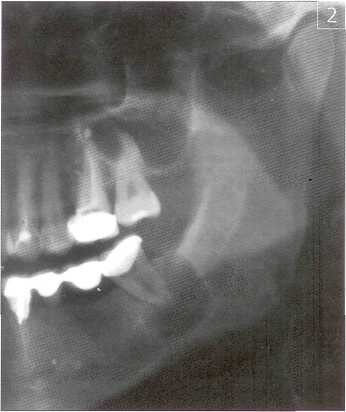

Клиническое течение послеоперационного периода у пациентов оценивалось на 3; 5 и 7 сутки после операции. На третьи сутки после оперативного вмешательства больные исследуемой группы [19 человек] отмечали отсутствие температурной реакции и болевого синдрома. Объективно: отек мягких тканей выражен слабо у 17 больных, а у 2 пациентов — отсутствовал совсем. В контрольной группе (21 человек) послеоперационный период протекал с подъемом температуры тела, выраженным отеком мягких тканей, больные отмечали необходимость приема обезболивающих препаратов. У трех пациентов контрольной группы на 3 сутки отмечается наличие гнойно-сукровичного отделяемого из линии швов, резко выраженный отек мягких тканей. Этим пациентам проведено дополнительное вмешательство, удалены швы, слизисто-надкостничный лоскут введен в костную полость, дальнейшее ведение — по типу цистотомии (под йодо-формным тампоном). По результатам рентгенологического обследования можно судить о состоянии костной ткани у пациентов до и после оперативного вмешательства. На ортопантомограмме больного С. до операции (рис. 2) определяется в области корня 37 зуба разрежение костной ткани с четкими контурами, размером 2,0 х 2,0 см., контуры нижнечелюстного канала не прослеживаются. Учитывая отсутствие костной ткани на протяжении 1/2 корня, 37 зуб в ходе операции был удален.

Рис.2 Ортопантомограмма больного С. до операции